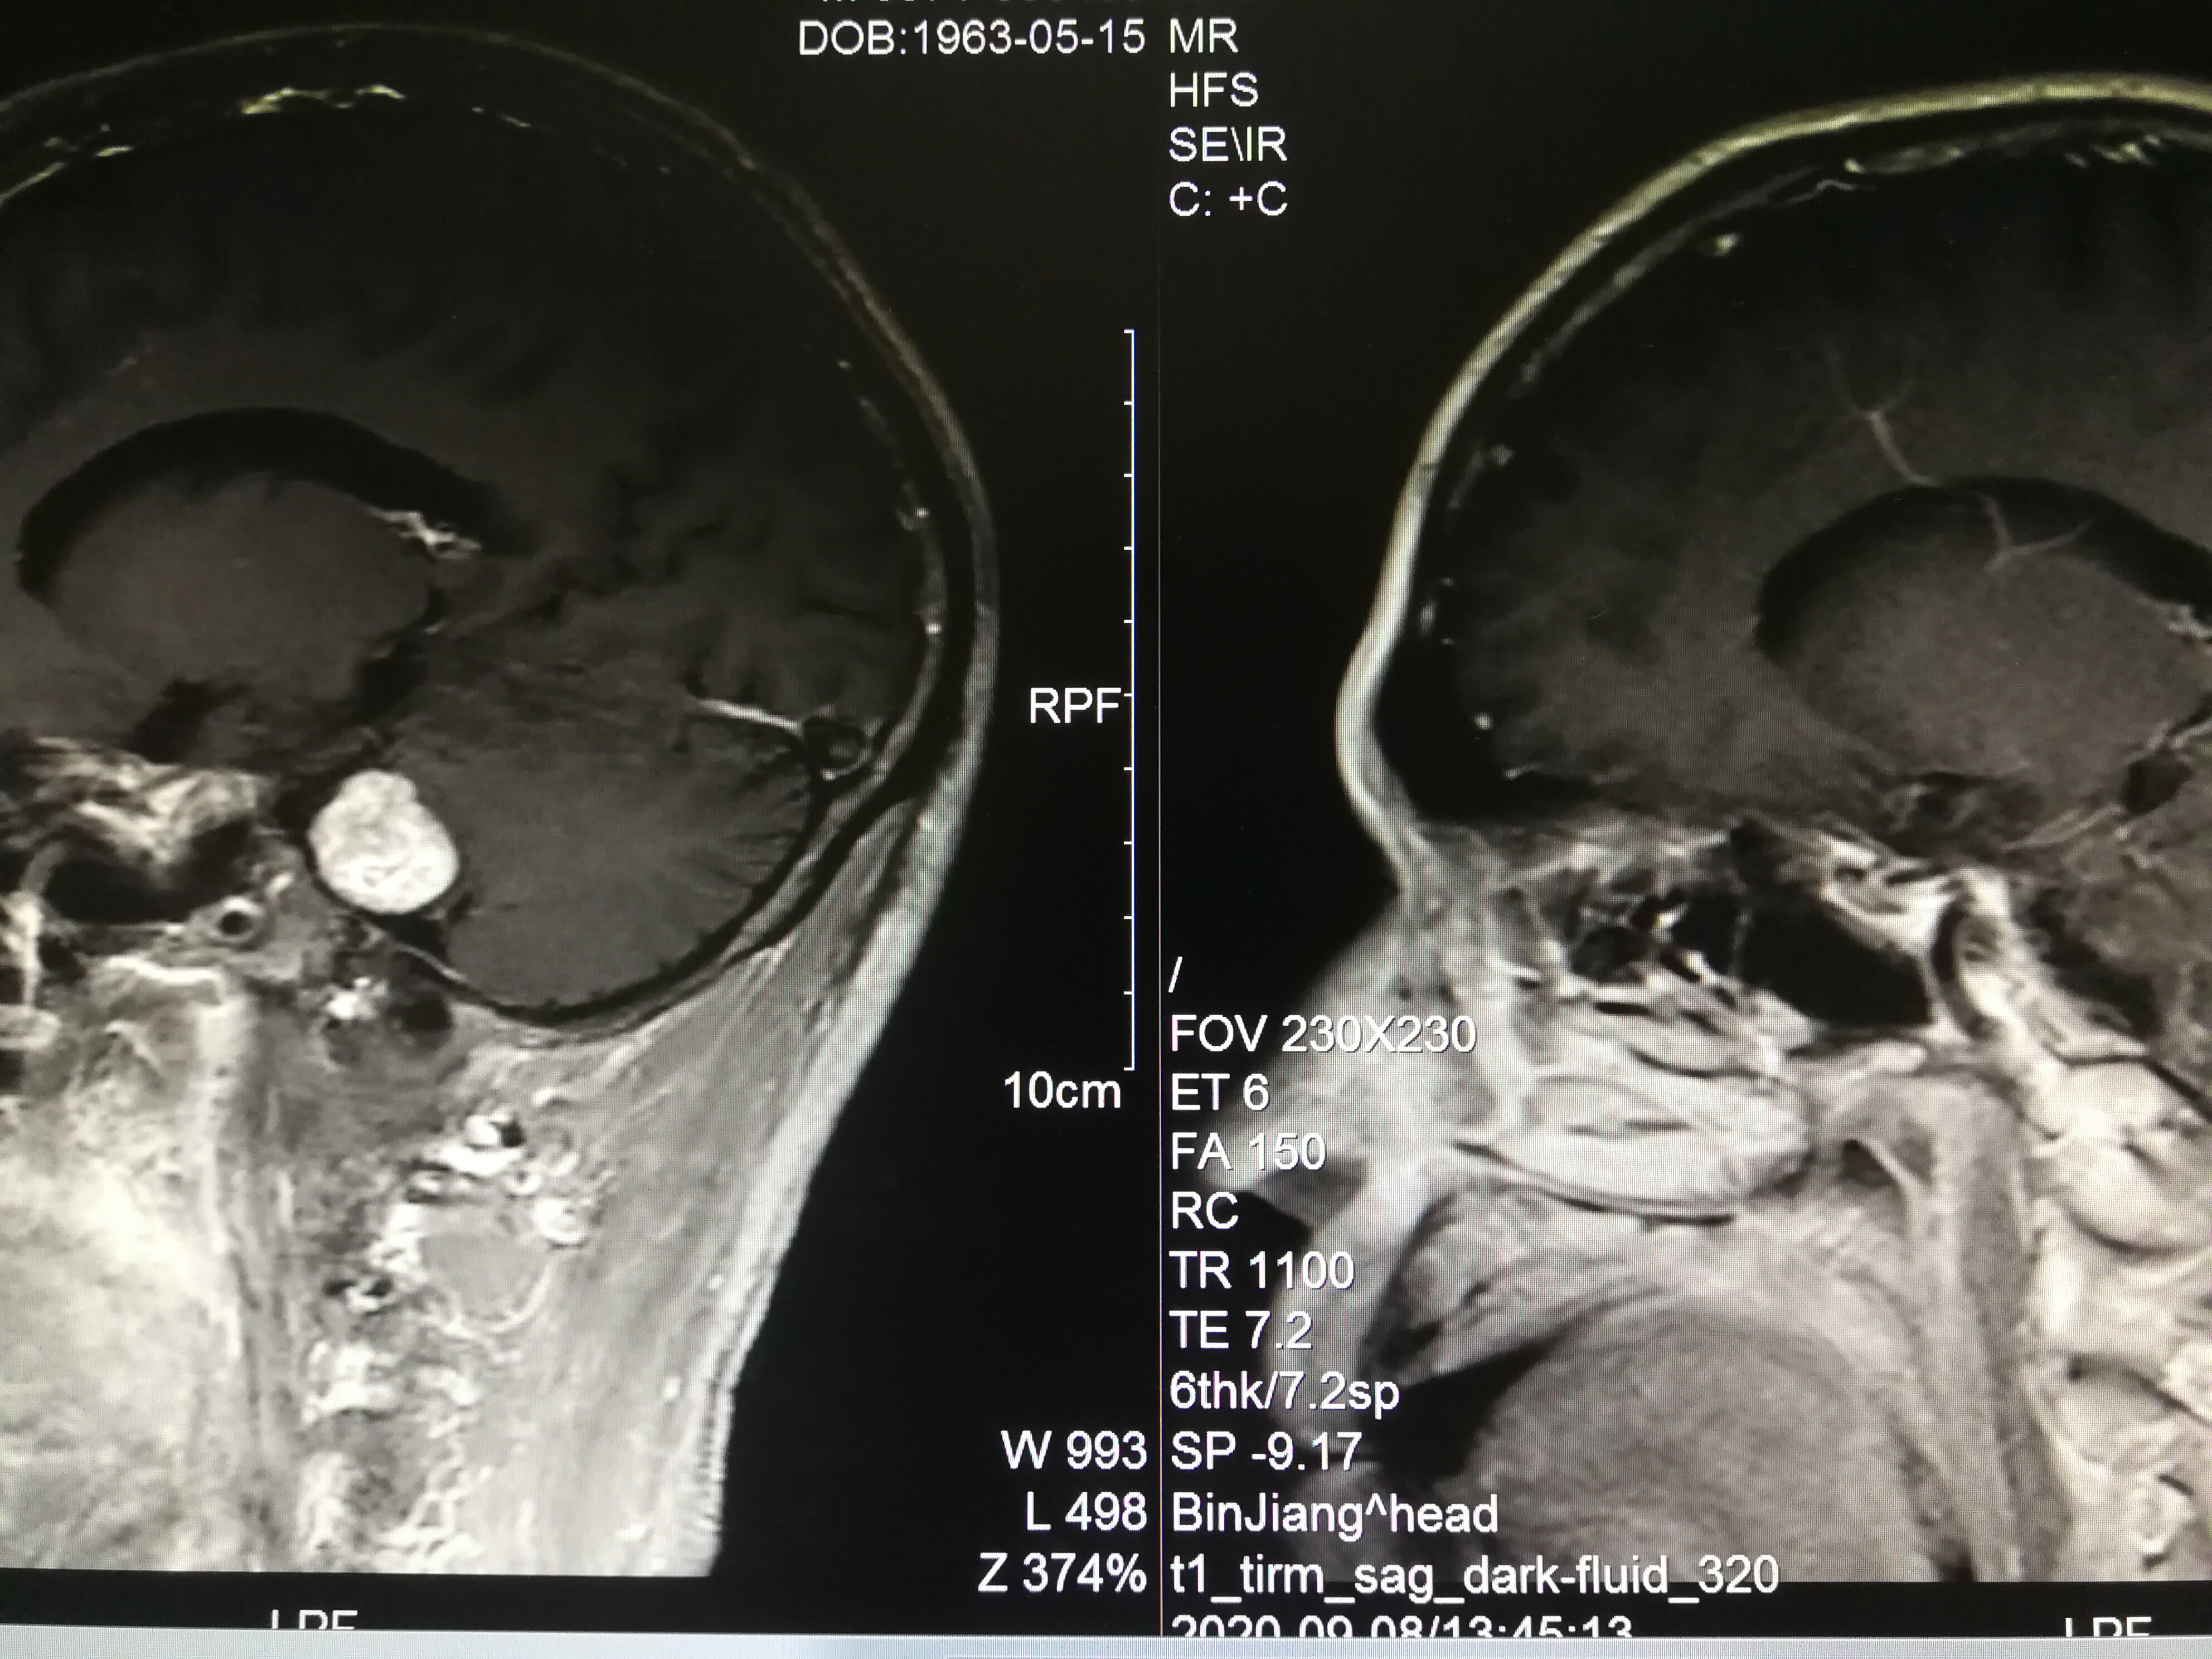

手术治疗听神经瘤是最主要的治疗方式,目前听神经瘤的手术已经非常成熟,只要没有明显的手术禁忌症首先应考虑手术治疗,并要求在电生理监测条件下完成手术,这样可以最大限度地保护面神经功能。以下是几例我们做的听神经鞘瘤手术前后核磁共振片子对照,除手术后听力不能恢复外,没有面瘫,脸部麻木,吞咽困难等颅神经症状,也无其他较明显的手术并发症发生。